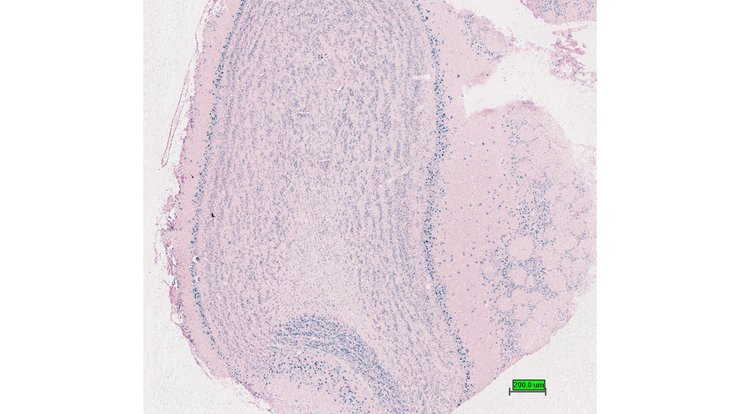

TS28: thymus Present UC Davis_1886735

Specimen UC Davis_1886736: postnatal adult; Ncoa5tm1.1(KOMP)Mbp/Ncoa5+ (more )

Structure Level Pattern Image Note

TS28: thymus Present UC Davis_1886736